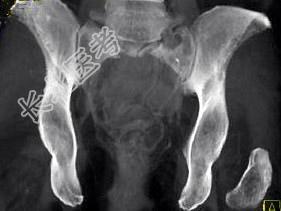

- 单项选择题患者60岁,如图所示, 该患者的鉴别诊断应除外 ( )

A、脊索瘤

B、浆细胞瘤

C、转移瘤

D、巨细胞瘤

E、以上都不是